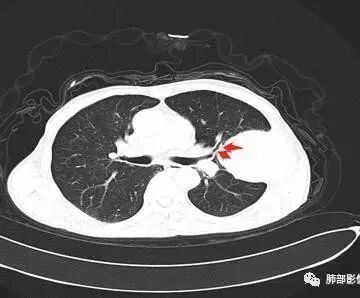

病灶与叶裂之间夹有上叶下舌段支气管、血管。舌段支气管后移,尖后段支气管前移,病灶将支气管撑开。

叶裂受压后移,提示病灶不来源于叶裂。

支气管推移-----提示外朝内

近端肺动脉受压外移,但是有部分进入病灶内-------提示与肺有千丝万缕的关系。

不符合,因为病灶的主体在肺内,而且胸膜在病灶的外侧为主

与胸膜非钝角相交

病灶的整体形态--肺内边界清晰,膨胀性为主

如果是外面长进来的,胸膜掀起的角度一般更大,呈钝角

我们换个角度讲,如果是胸壁肋骨来源,病灶外朝内生长,并且朝内生长这么大,按理说应该是内侧侵袭性强,外侧侵袭弱。但是看这个病灶,外侧边界反而不清,内侧边界清,整个形态不太符合肋骨来源,而且胸膜局部增厚也不太符合胸壁来源。我认为肋骨来源应该以肋骨为中心,偏侧可以,但不会这么明显。而且血供也不一致,应该是肋间或胸壁动脉明显。

肋骨内侧面破坏为主,朝外有轻微的推移迹象。我觉得胸壁来源的放后面,特别是支气管的堵塞,这是肺外病变很少见的,SFT也有,罕见。

鳞癌,与吸烟关系密切,起源于支气管粘膜上皮,典型的征象就是支气管截断,周围型鳞癌往往体积较大,有时候与支气管关系不好判断,需要多平面重建看支气管的关系。